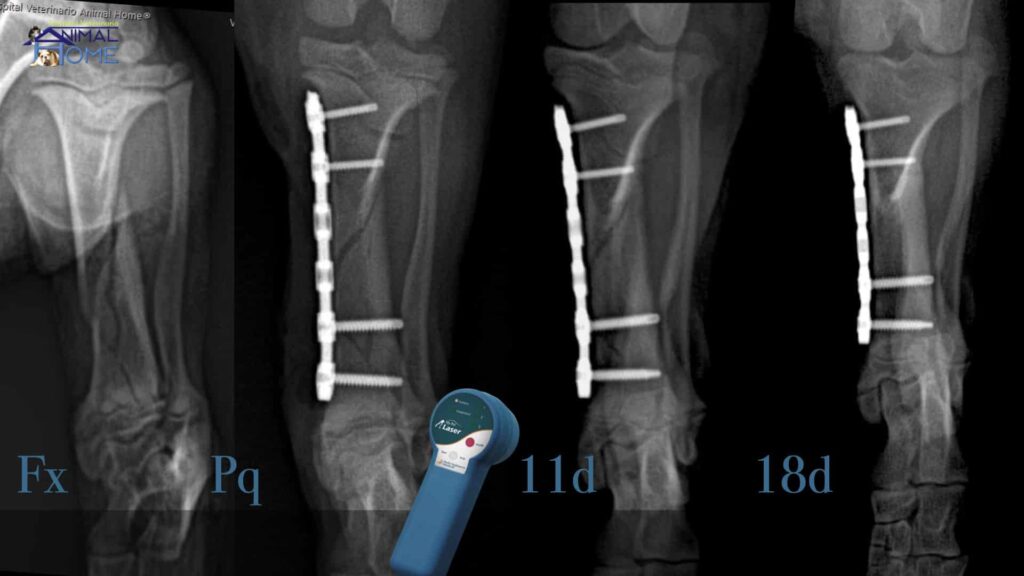

- Casos Clínicos Reales: Una parte fundamental del aprendizaje se basa en la discusión y resolución de casos clínicos auténticos. Esto permite a los estudiantes aplicar los conocimientos teóricos a situaciones prácticas, desarrollar habilidades de razonamiento diagnóstico y planificar estrategias de tratamiento.